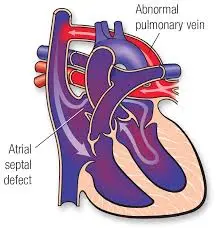

Value added benefits of the ASD Surgical Closure Open Surgery:

Ø Doctor consultation charges

Ø Lab tests and diagnostic charges

Ø Room charges inside hospital during the procedure

Ø Surgeon Fee

Ø Nursing charges

Ø Hospital surgery suite charges

Ø Anesthesia charges

Ø Routine medicines and routine consumables (bandages, dressings etc.)

Ø Food and Beverages inside hospital stay for patient and one attendant.

Extra benefits:

ü Interpreter

ü Visa assistance

Ø Site tourism of the city

Ø Follow up with the doctor

Ø Airport pick up and drop

Ø Free online consultation with the doctor

Ø Priority appointments with the doctor

Ø Room upgrade from sharing to private

Value added benefits of the ASD Closure:

Ø Doctor consultation charges

Ø Lab tests and diagnostic charges

Ø Room charges inside hospital during the procedure

Ø Surgeon Fee

Ø Nursing charges

Ø Hospital surgery suite charges

Ø Anesthesia charges

Ø Routine medicines and routine consumables (bandages, dressings etc.)

Ø Food and Beverages inside hospital stay for patient and one attendant.

Extra benefits:

ü Interpreter

ü Visa assistance

Ø Site tourism of the city

Ø Follow up with the doctor

Ø Airport pick up and drop

Ø Free online consultation with the doctor

Ø Priority appointments with the doctor

Ø Room upgrade from sharing to private